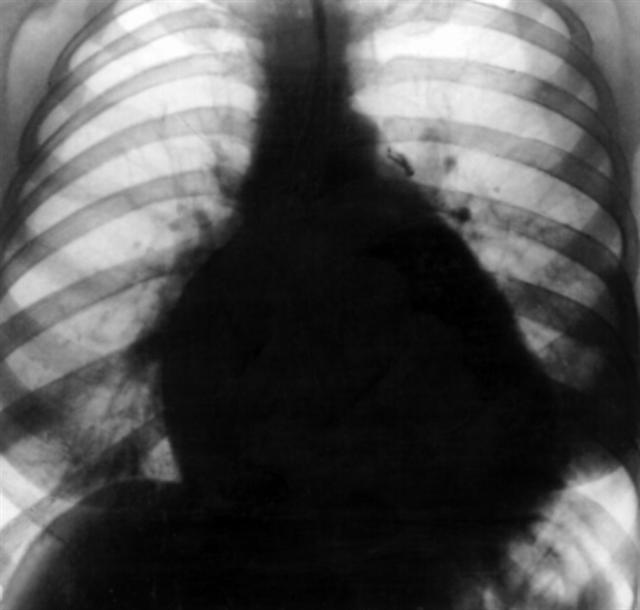

Рис. 5а). Рентгенограмма грудной клетки больной с хронической митральной недостаточностью (передняя проекция): тень сердца расширена в поперечнике в обе стороны, справа выбухает дуга левого предсердия, легочный ствол почти не выбухает.